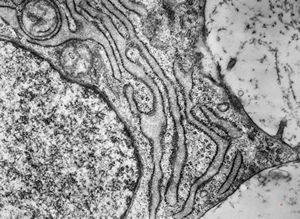

M,19y. | chondrocyte - chondrosarcoma - jaw